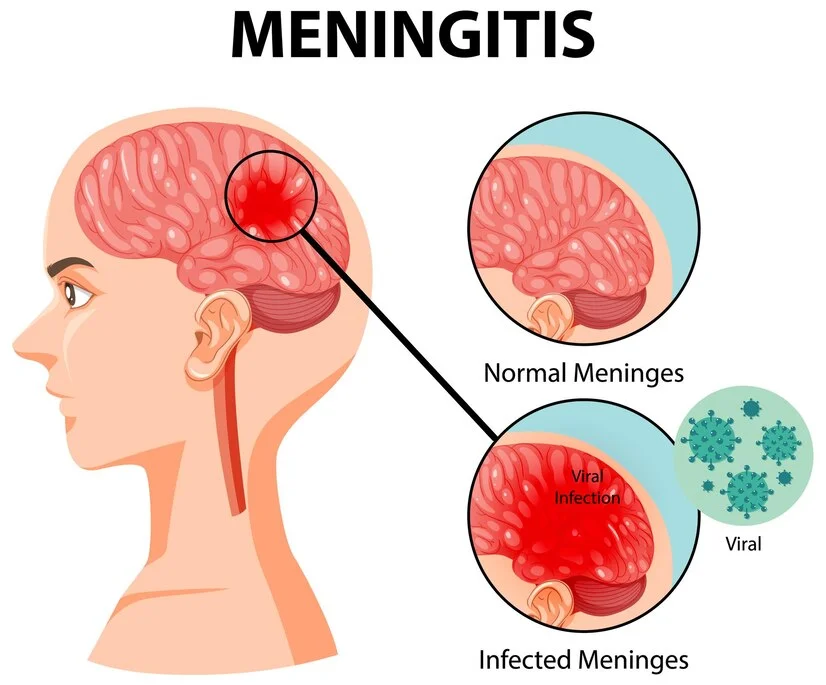

Understanding Meningitis: Causes, Symptoms, and Treatment Meningitis is a serious condition that needs immediate